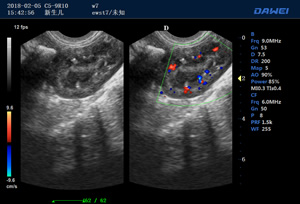

出色的獸用臨床應用

·支持B、C、PW、CW、寬景成像

·適用于各種動物的臨床腹部、胸腔,心臟、肌腱、小器官、眼球、生殖系統等的檢查